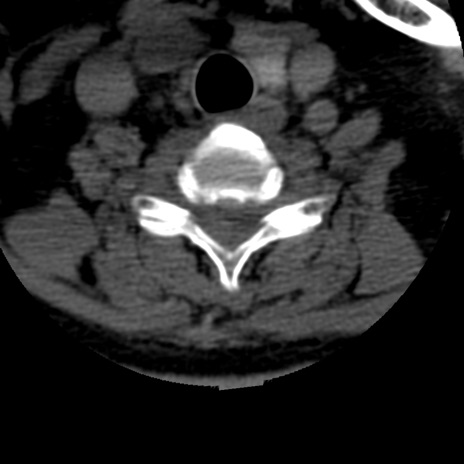

症例50 頚椎CT(横断像)

【症例】60歳代女性

【主訴】後頭部〜右後頸部にかけての痛み

【現病歴】本日飲食店でコーヒーを飲んでいたところ、突然後頭部〜右後頸部にかけて痛みが出現し、右上肢の感覚障害を伴ったため救急要請。

【身体所見】脳神経学的に明らかな異常所見を認めず。右上肢に軽度の感覚障害あり。

異常所見と診断は?

頚椎CT